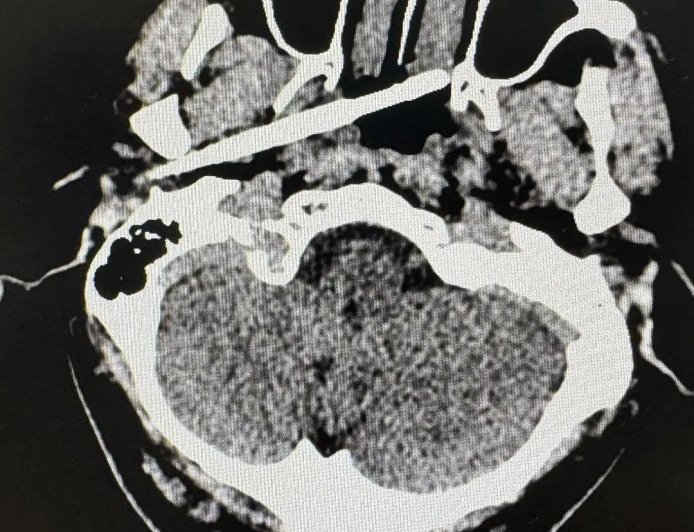

男子被一根筷子从耳部插入颅底 距动脉仅5毫米 医生成功救回

近日,南方医科大学珠江医院创伤中心成功救回了一名被筷子从耳部插入颅底的男子。据悉,筷子不仅穿透了耳部骨质,断端还残留在体内,筷子尖端距离颈内动脉仅5毫米,颈内动脉是大脑供血的主干线之一,一旦破裂,可导致瞬间大出血死亡,患者可能在短时间内死亡。接诊后,创伤中心迅速启动严重创伤救治...